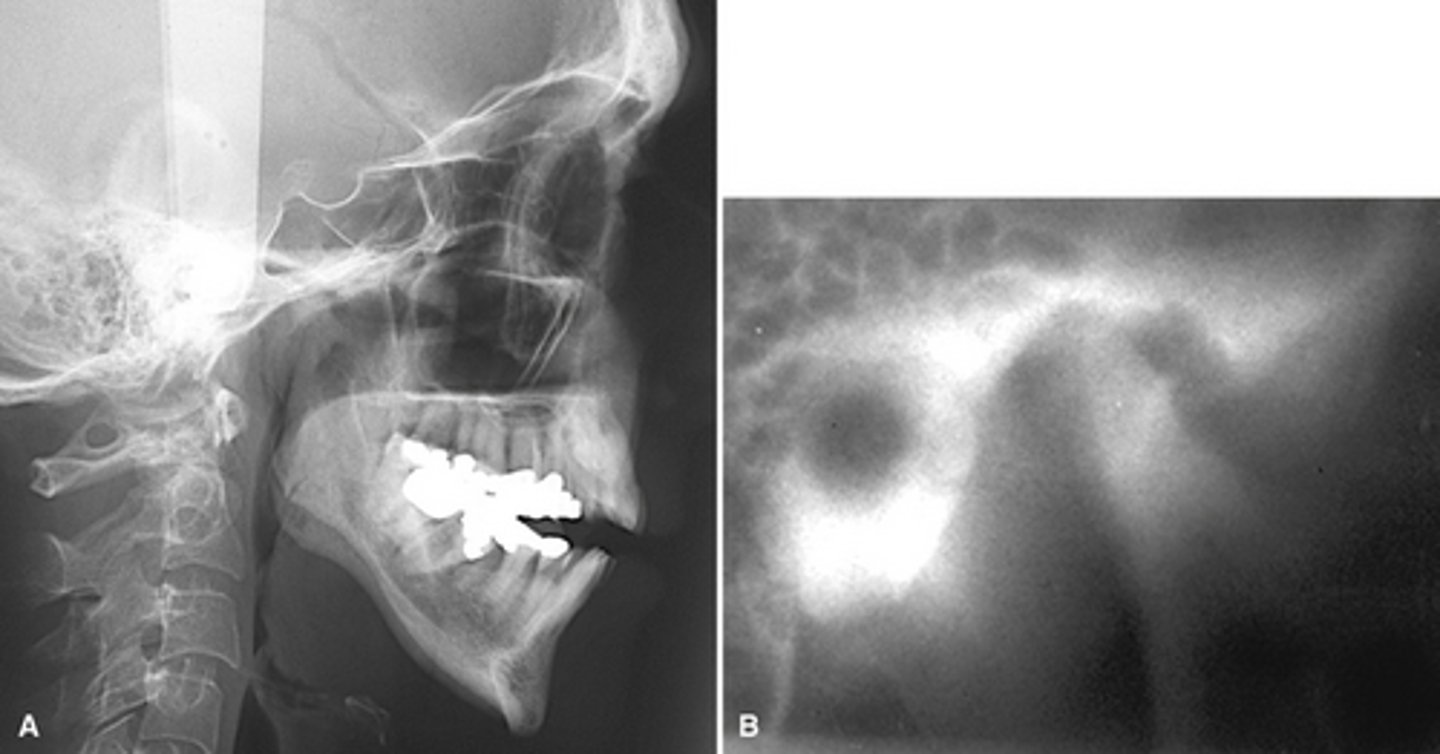

RA (rheumatoid arthritis)

Image A shows a lateral ceph where the patient has a steep mandibular plane and anterior open bite.

Image B shows erosion of the temporal component of the TMJ

What is the diagnosis of the patient based off these radiographs and what are the features?